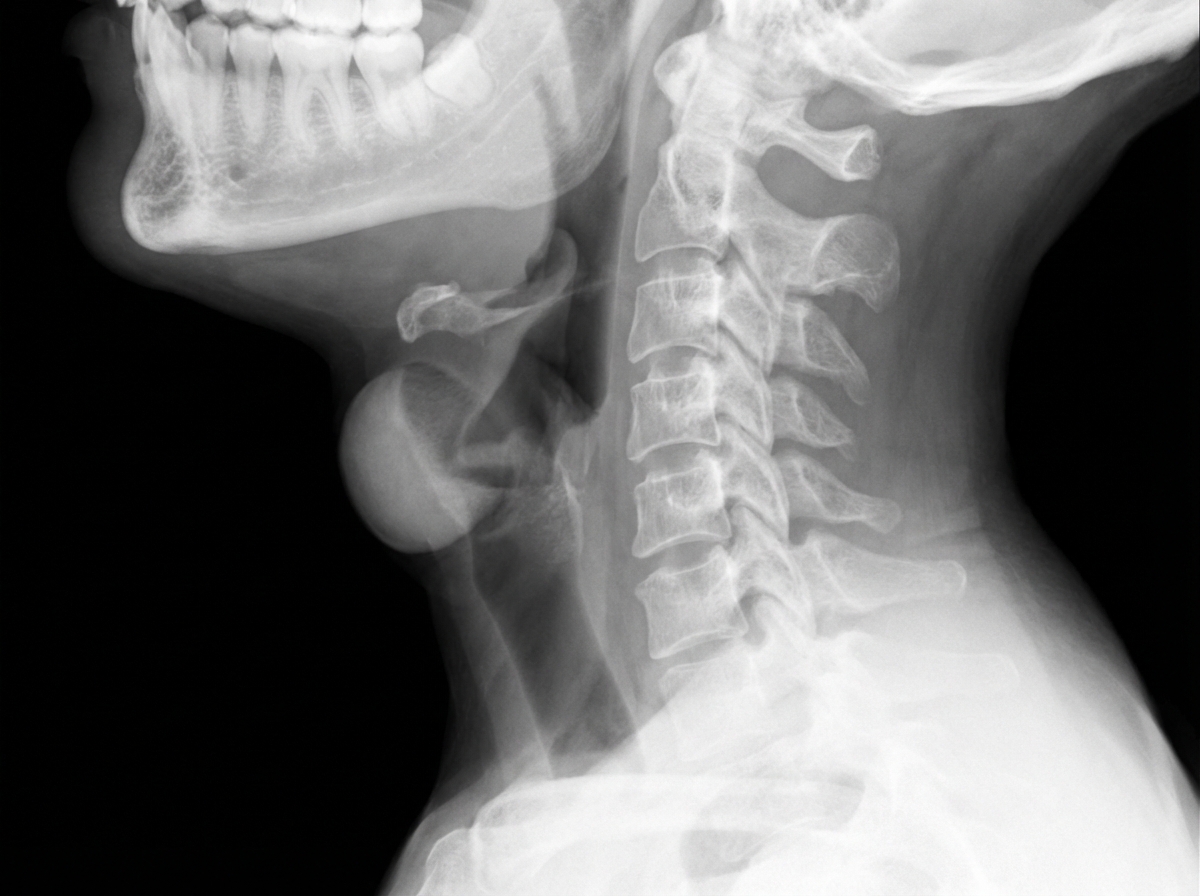

A 4-year-old child presents to the emergency department with high-grade fever, respiratory difficulty, and noisy breathing. An X-ray of his neck is shown below. What is the most probable diagnosis?

Explanation: ***Epiglottitis*** - **High-grade fever**, **respiratory difficulty**, and **noisy breathing** in a child form the classic triad of epiglottitis, often caused by **Haemophilus influenzae type b**. - The lateral neck X-ray shows the characteristic **"thumbprint sign"** indicating swollen epiglottis, which is pathognomonic for epiglottitis. *Recurrent papillomatosis* - Typically presents with **progressive hoarseness** and **chronic respiratory symptoms** rather than acute high fever. - X-ray would show **multiple nodular lesions** in the larynx, not the thumbprint sign of epiglottal swelling. *Croup* - Usually presents with **barking cough** and **low-grade fever**, not the high-grade fever seen here. - Lateral neck X-ray would show the **"steeple sign"** (subglottic narrowing), not the thumbprint sign of epiglottal swelling. *Tonsillitis* - Primarily causes **sore throat** and **difficulty swallowing** rather than respiratory distress and noisy breathing. - X-ray findings would not show epiglottal involvement; diagnosis is typically made by **clinical examination** of enlarged tonsils.